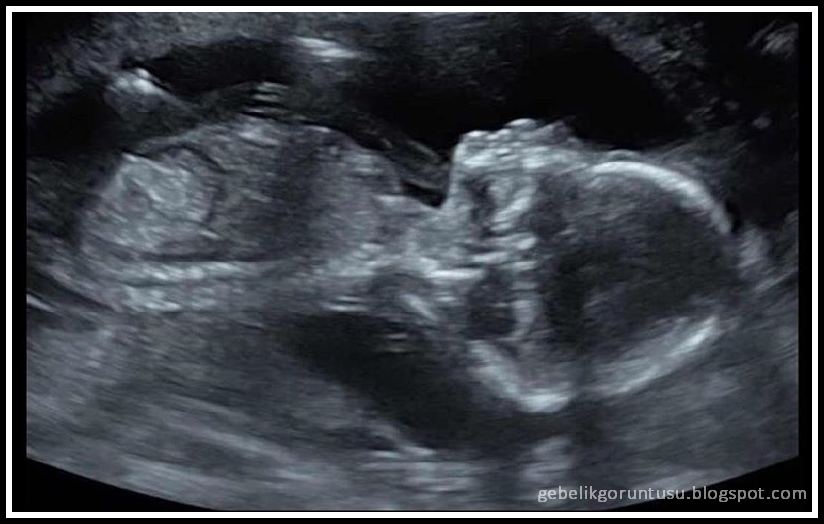

17 Haftalık Bebek Ultrason Görüntüsü

17 Haftalık Bebek Ultrason Görüntüsü.